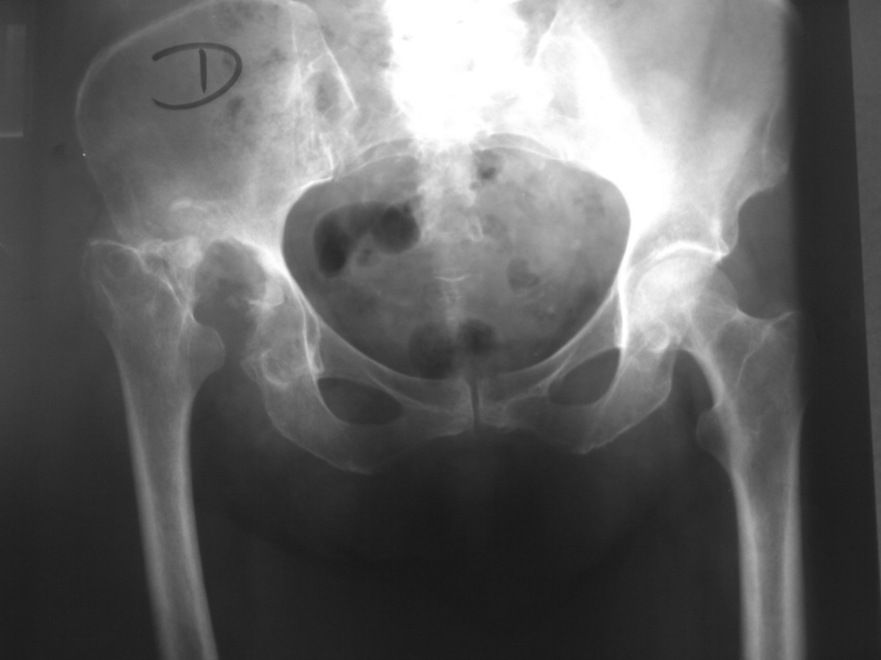

Las radiografías simples en proyección anteroposterior (AP) de la pelvis y laterales de cadera son los primeros pasos en la evaluación por imagen. La radiografía (AP) refleja la magnitud de la afectación y determina el grado de artrosis. Las laterales evalúan la cobertura lateral.